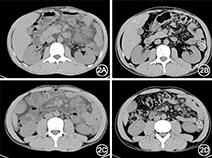

患者男性,35岁,因"间断上腹部隐痛、乏力伴体重下降2年"于2014年9月26日入院。患者近2年间断上腹部隐痛,伴乏力、体重下降。腹部增强CT:肠系膜根部、腹主动脉旁及双侧髂血管旁见多发类圆形软组织结节影,增强后轻度强化。曾于2014年8月在外院行剖腹探查+肠系膜肿块切除活检术。术中见肠系膜上弥漫性、多发性肿块,最大约5.0 cm × 5.0 cm,为囊性,内为浑浊囊液(图1)。自发病以来,无发热、皮下结节等。既往体健。长期大量饮酒史。入院体检:一般情况好,心肺未见异常;上腹部及脐周深压痛,肠鸣音减弱。实验室检查:ALT 111 U/L,AST 74 U/L;ESR、超敏C反应蛋白、补体、免疫球蛋白及IgG4均正常;结核菌素试验(-),血结核特异性淋巴细胞干扰素(A+B)0 SFC/106单个核细胞(即经结核分枝杆菌特异性RD1基因编码抗原肽段库A和B刺激后,未检测到释放IFNγ的特异性淋巴细胞,提示不支持结核感染)。腹部增强CT+三维重建:肠系膜区脂肪密度增高、间隙模糊,肠系膜根部多发类圆形肿块,符合脂膜炎,腹盆腔积液。病理科会诊:(肠系膜)网膜组织,大量组织细胞、淋巴细胞浸润伴滤泡形成,可见炎性坏死及渗出物,局部纤维增生,提示慢性炎伴局部急性炎。免疫组化:S-100部分(+),CD68(+),CD3(+),CD20(+),CD138(散在+),SMA (梭形细胞+),Calretinin(-),AE1/AE3(-),CD21(滤泡+),Ki-67指数为10%。诊断为肠系膜脂膜炎。予泼尼松40 mg/d治疗1个月,患者腹痛缓解,复查腹部CT(图2),显示原肠系膜肿块明显缩小,肠系膜区脂肪密度增高、间隙模糊明显减轻,原腹腔积液吸收。泼尼松逐渐减量,1年后随访患者无腹痛等不适症状,ALT 48~85 U/L,AST 29~48 U/L。

本例患者主要表现为慢性腹痛,CT发现肠系膜根部肿物存在典型的脂肪环形征、肿块假包膜。活检病理除外淋巴瘤、结核、腹膜转移癌等疾病,而且为肠系膜组织慢性炎症伴局部急性炎,MP诊断明确。本病为良性疾病,多数预后良好。治疗方面,国内外对于本病尚无统一治疗方案,治疗经验较少。据文献报道,部分存在自限性,无需特殊治疗可自发缓解[2]。如出现肠梗阻等症状,可考虑外科手术治疗[3,4],药物治疗的目标是控制炎症反应,主要治疗药物包括糖皮质激素、免疫抑制剂、秋水仙碱、孕激素、沙利度胺等。本例患者虽一般情况良好、症状不重、无发热及炎症指标升高,但考虑到已出现肠鸣音减弱、肠腔扩张积气、腹腔积液等表现,腹部肿块较多、较大,外科不能全部清除,病情可能进展出现肠梗阻、肠系膜缺血坏死等严重并发症,遂予泼尼松治疗。3个月后患者症状完全缓解,复查影像学明显好转。本病例提示对于MP出现弥漫性多发性肠系膜肿块,即使没有明显全身炎症反应,也可考虑短期糖皮质激素治疗,中等剂量糖皮质激素可减轻肠系膜脂肪组织炎症反应,利于缩小肿块,缓解腹痛症状。另外,本例患者伴有肝功能异常,表现为ALT、AST升高,行肝活检提示慢性炎症,尚未见文献阐述MP与肝损伤之间的相关性。本例患者经糖皮质激素治疗后,症状缓解,影像学改善,同时转氨酶有下降趋势,不能除外两者可能有联系。目前仅有少数文献提及MP可能与肝硬化、胆结石等疾病有关[5]。但本例患者既往有长期大量饮酒史,不能排除酒精性肝病可能,因此MP与肝病的关系尚待进一步探讨。